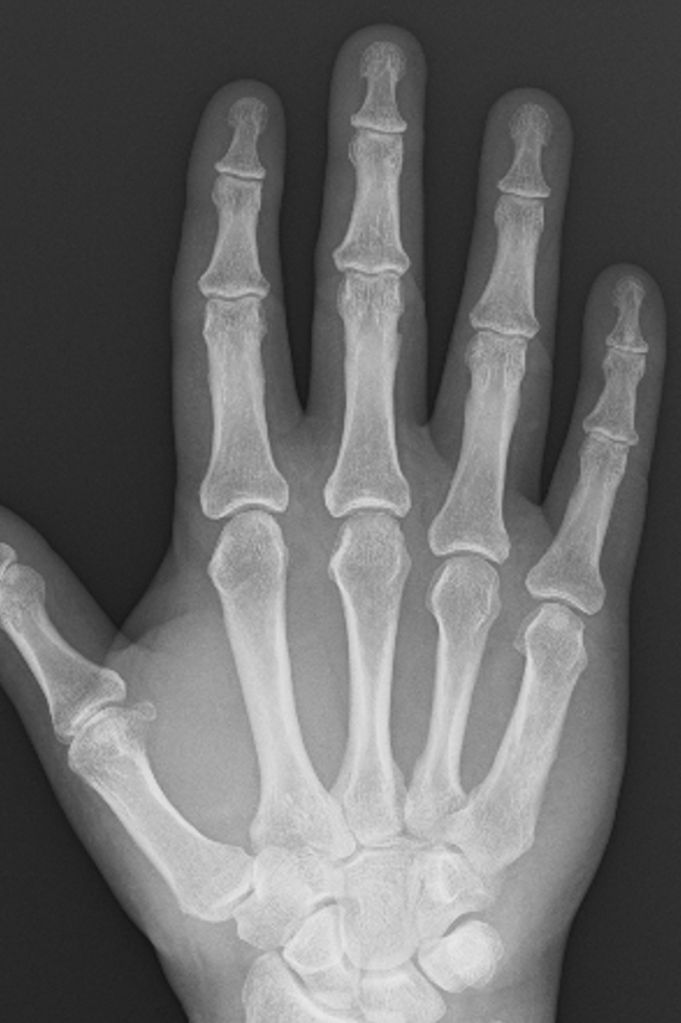

How do we know whether there is arthritis in a joint from an X-ray?

Osteoarthritis has a very characteristic appearance on X-rays, making it relatively easy to exclude any other types of arthritis.

There are four features of osteoarthritis on an X-ray:

– Loss of joint space

– Sub-chondral sclerosis

– Osteophyte formation

– Cyst formation

Loss of joint Space

In young patients, there are thick cartilage caps on the ends of the bones within the small joints of the hand. With age, these cartilage caps slowly wear from constant use, despite the body’s regenerative processes. A normal joint, therefore, has much less cartilage at 50 than at 20, and by the time people reach 80+ years, there is often very little cartilage left.

The GAP between the bones on an X-ray represents the space occupied by the cartilage, and it is very easy to predict how much cartilage is left in a joint simply by looking at the amount of space between the bones – the more space the more cartilage, and generally speaking the more healthy the joint.

Subchondral Sclerosis

Subchondral simply means ‘under the cartilage‘, and sclerosis is the name given when bone appears thicker or whiter on an X-ray. When cartilage is lost from the joint, bone articulating with bone triggers a process where the body tries to increase the density of the remaining bone to protect it – on an X-ray, this gives an appearance of whiteness around the joint, because less X-rays can pass through this thickened bone and make it to the X-ray plate.

Osteophyte Formation

The stability of a joint depends on the shape and fit of the bone on either side of the joint, and the soft tissues around the joint. In particular, the small joints of the hands have collateral ligaments on either side of the joint, and a tough sheet of fibrous cartilage (volar plate) on the palm side of the joint. These soft tissue structures prevent abnormal movement in the joint.

Where the joint surfaces have worn away, the ligaments and volar plate become slightly too long for the remaining gap, allowing movement of the joint in an abnormal way. The body responds by laying extra bone around the joint in order to make it stable. The extra bone is called an osteophyte, and this usually makes the joint stiffen up considerably.

Cyst Formation

Cysts represent areas where the bone has been resorbed or dissolved away by the body. They occur around the arthritic joint, and are thought to occur in response to increased pressure around the arthritic joint. This, in turn, can interfere with the normal blood flow and facilitate cyst formation.